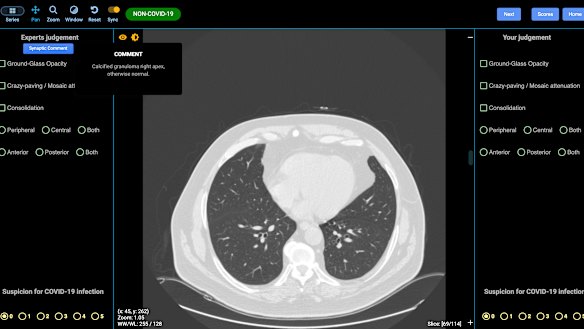

A lung CT showing no sign of COVID-19. DetectED-X

Leading University of Sydney academic radiologist and CovED co-creator Professor Stuart Grieve said there are three predominant signs of COVID-19 that show up on lung scans.

If a patient has the right history of risk, the first sign of an early COVID-19 infection is called “ground glass opacity”, where the normally black space in the lungs appears “like a frosted window”.

The second sign is called “crazy paving”, because Professor Grieve said it looks “exactly like that” - patches of lung that are whiter in appearance than others, which shows a more advanced stage of the disease.

The third sign is called consolidation, where the lung is filled with mucus and appears white with no air able to enter that area, Professor Grieve said.